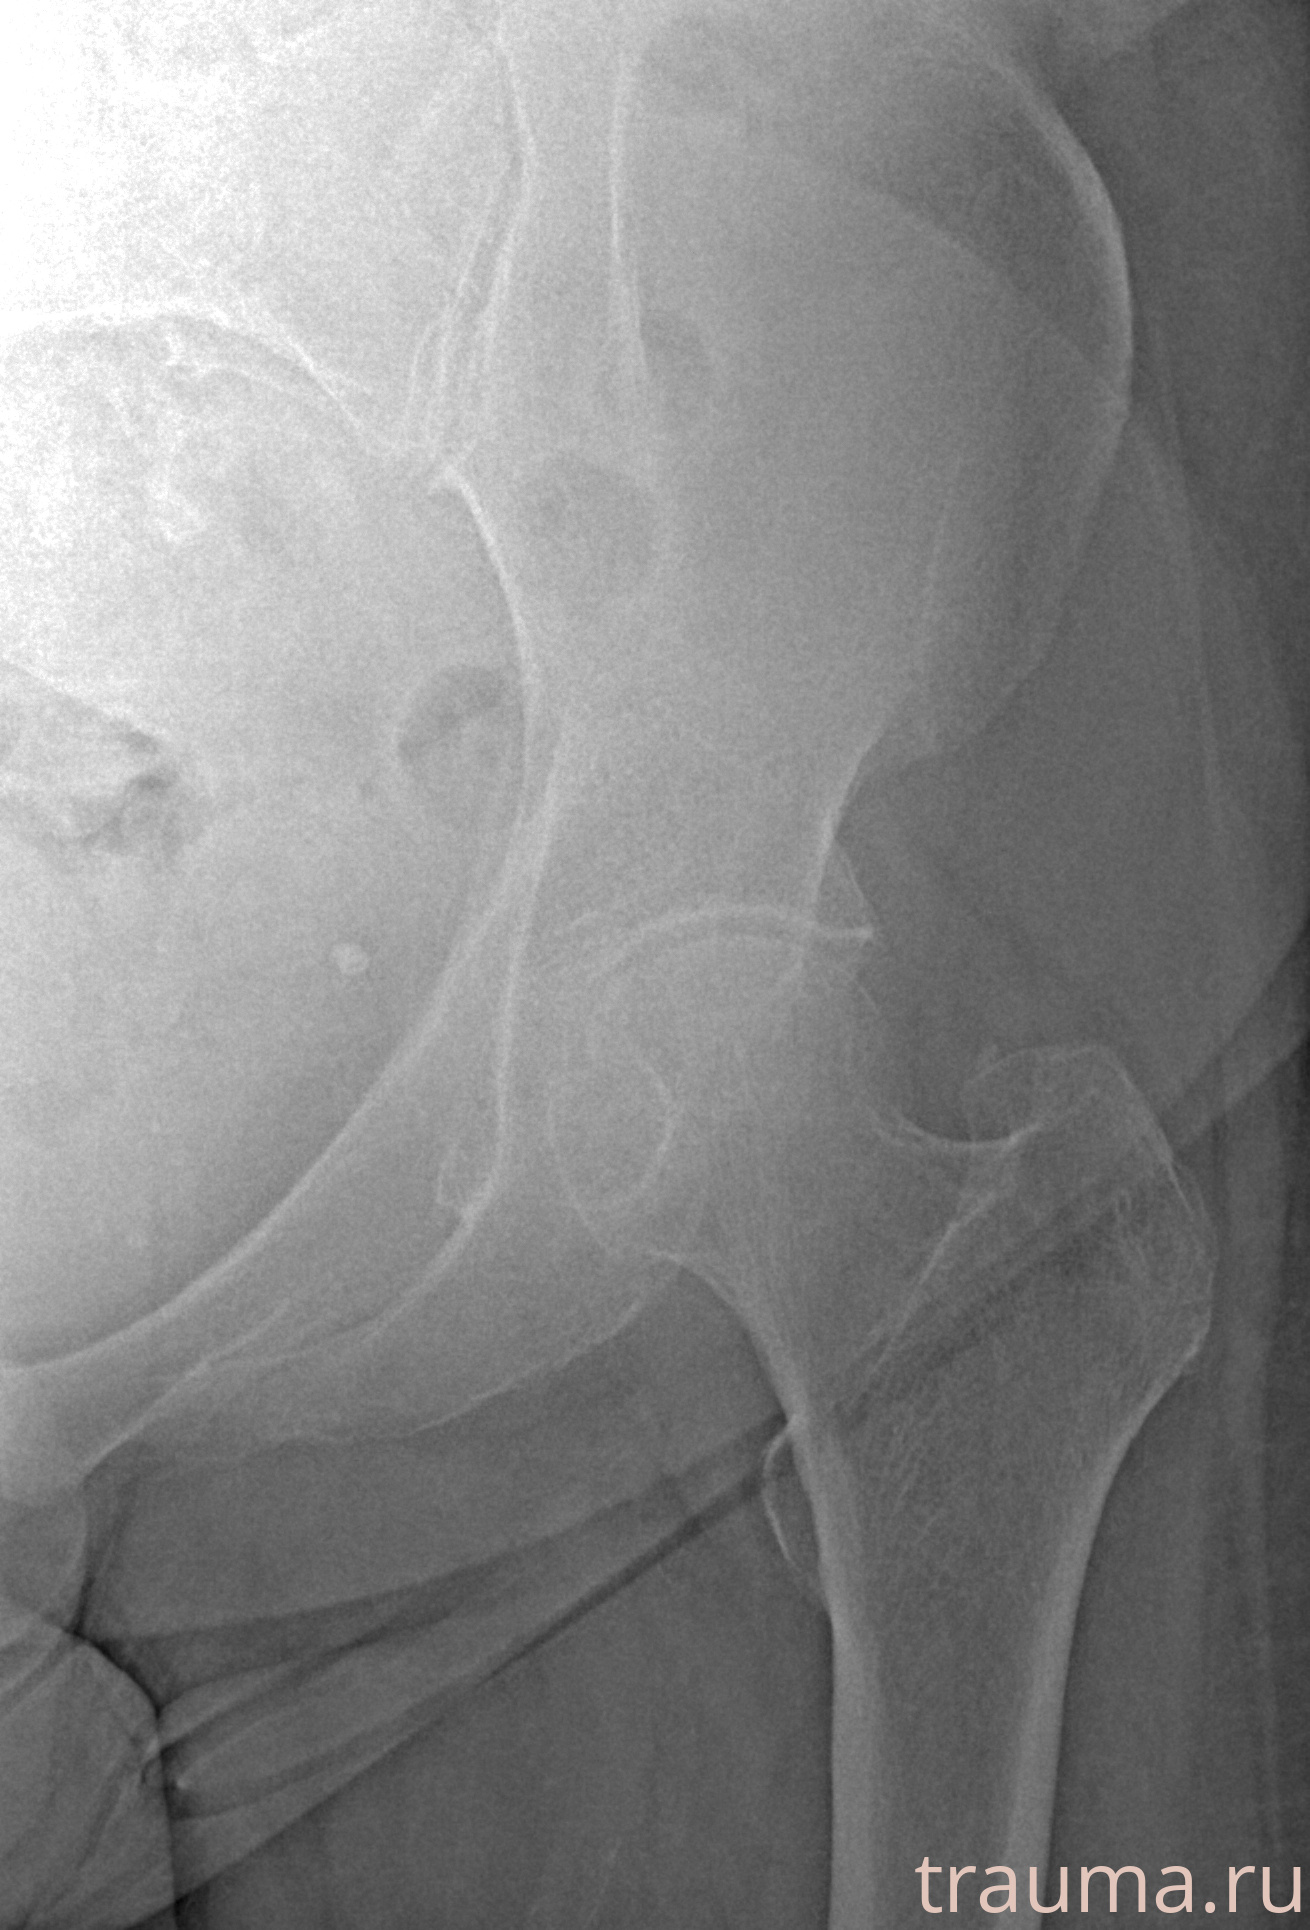

Рентгенограммы

Рентген на дому: по вашему адресу приезжает врач-рентгенолог, травматолог-ортопед с мобильным рентгеновским аппаратом, проводит диагностику травмы или заболевания, делает необходимые рентгенограммы, дает рекомендации по дальнейшему лечению. Получить качественные снимки в домашних условиях возможно благодаря уникальной методике, разработанной МосРентген Центром для института  Склифосовского